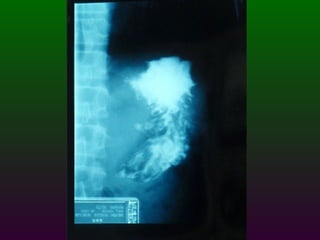

SEGD ENFERMEDADES DEL ESTÓMAGO INFLAMACIÓN NEOPLASIAS: Pólipos benignos Carcinoma Linfoma Leiomiomas TRASTORNOS DIVERSOS: Gastritis atrófica Crónica:   Gastritis hipertrófica   Gastritis cáustica   Vólvulos

SEGD ENFERMEDADES DELESTÓMAGO INFLAMACIÓN NEOPLASIAS: Pólipos benignos Carcinoma Linfoma Leiomiomas TRASTORNOS DIVERSOS: Gastritis atrófica Crónica: Gastritis hipertrófica Gastritis cáustica Vólvulos